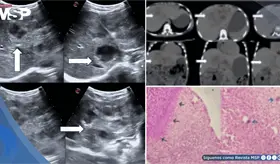

Las imágenes sugirieron un tumor con hueso, grasa y tejido cerebral dentro del recto, confirmando un diagnóstico poco común que solo se documenta en uno de cada 35.000 a 40.000 casos a nivel mundial.